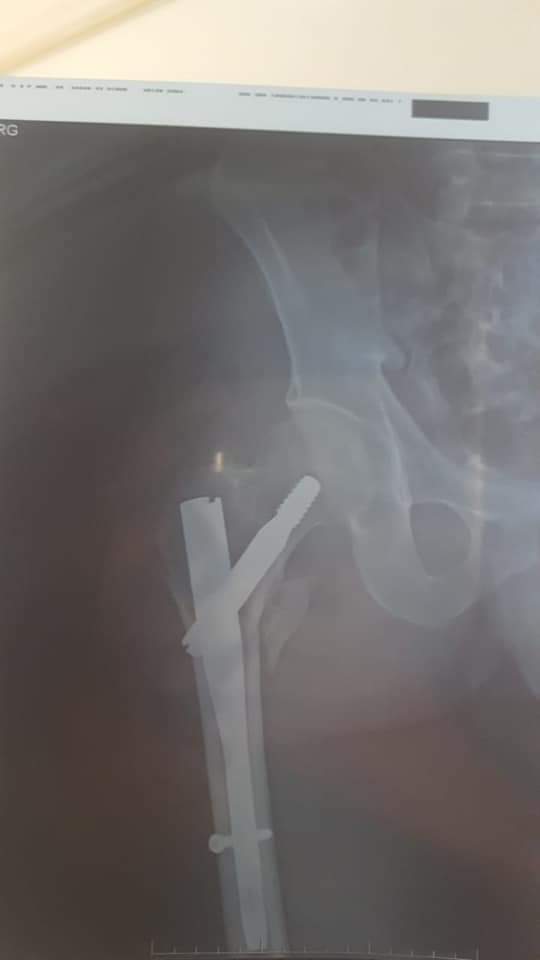

وأجريت هذه العملية تحت رئاسة الطبيب الجراح “البشيري محمد” اخصائي في جراحة العضام لفائدة مريض يبلغ عمره 55 سنة مصاب بكسر على مستوى الفخد الأيمن (Fracture pertrachanterienne ).

وعمل الطاقم الطبي على تثبيت الطرف العلوي من عضم الفخد جراحيا بواسطة مسمار غاما ( clou gamma ) لفائدة المريض.